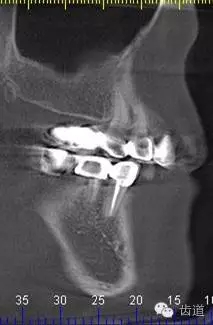

2、45,46術(shù)前片顯示根管上段充填物,根管影像不清晰,少許根尖暗影

5、右下頜側(cè)面觀

6、45,46,47牙片

7、45,46,47CBCT